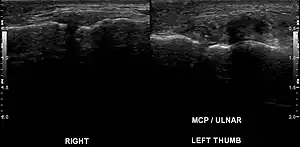

Stener lesion on left thumb in ultrasound

Stener lesion in an ulnar collateral ligament injury of the thumb